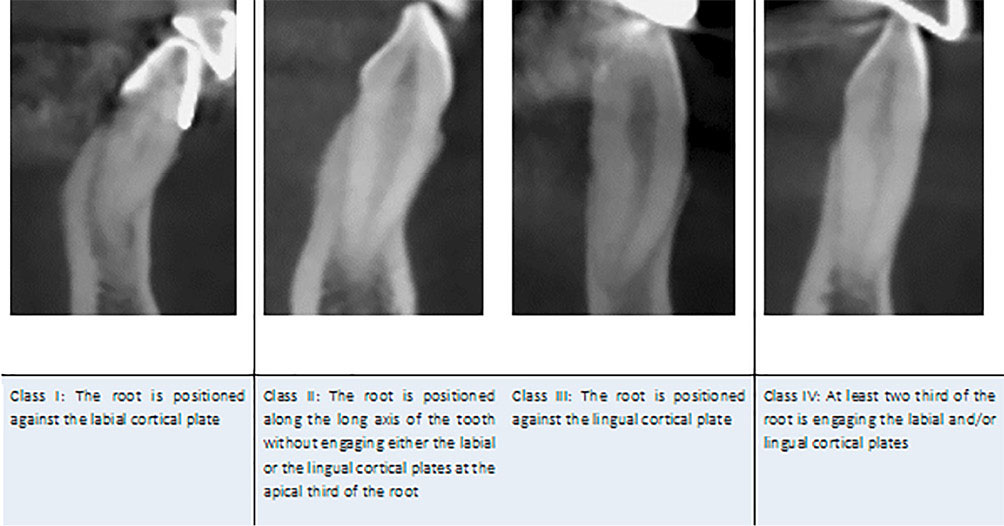

The apex position was classified as classes I, II, III, and IV according to the sagittal inclination of the apex of the tooth long axis (Figure 4). In the class I category, the root is positioned against the labial cortical plate. In the class II category, the root is positioned along the long axis of the tooth without engaging either the labial or lingual cortical plate at the apical third of the root. In the class III category, the root is positioned against the lingual cortical plate, and if at least two-thirds of the root engage the labial and/or lingual cortical plate, it is classified as class IV (Figure 4).

japid-12-65-g004

Figure 4. Kan’s classification of apex sagittal positioning.

The apex was positioned buccally (Class I) in 4.6% of the samples, along the long axis of the tooth (Class II) in 78.2%, lingual (Class III) in 0.7%, and Class IV in 16.3% of the cases.